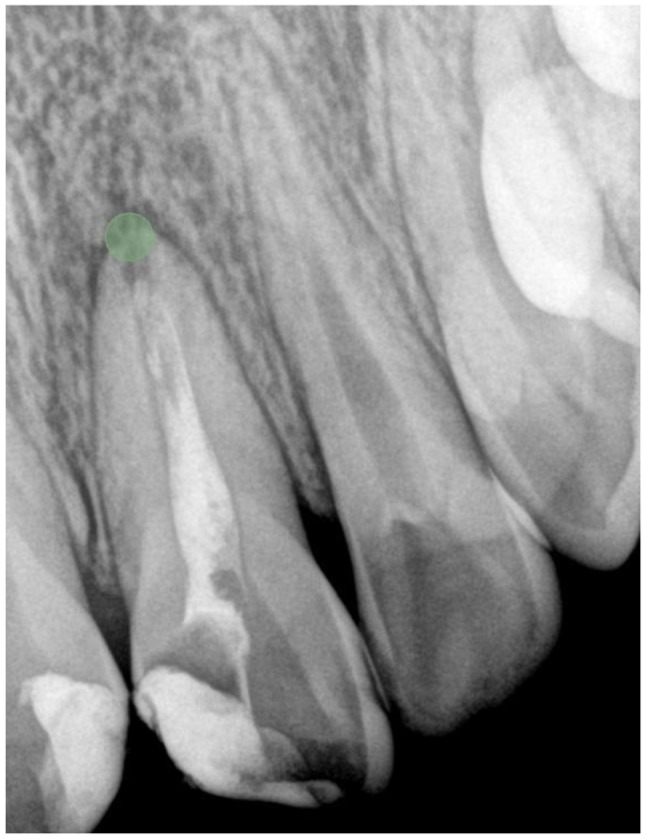

Radiomics-based classification of pediatric dental trauma in periapical radiographs: a preliminary study.